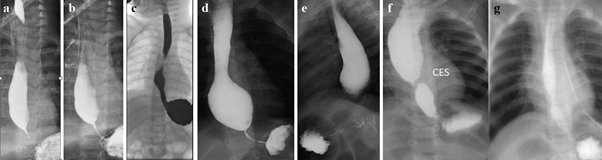

Figure 2 shows examples of radiographs of children with GERD whose analysis excludes the possibility of EA.

Figure 2 Typical radiographs showing GERD in 19 patients.

(a) A 14-year-old girl with dysphagia and vomiting. Based on radiological symptoms (dilated esophageal body, stasis of the contrast in it, a bird’s beak deformity in the EGJ) as well as on typical findings on HRM (absence EGJ relaxation), EA was diagnosed. After repeated pneumodilations of the LES dysphagia completely resolved.38

Analysis. Since the height of L-1 at this age is 2.2 cm, therefore the height of D-11 is ≈ 2 cm. What the authors called bird’s beak deformity (white arrow) is an open LES, through which the contrast agent freely fills the stomach. The length of the LES is 1 cm, which is significantly shorter than the normal LES at this age - 2.3 – 2.9 (2.45±0.11 cm). A sharp shortening of the LES indicates GERD, which is also confirmed by the presence of phrenic ampulla {a}. The esophagus is dilated just above the peptic narrowing between the two blue arrows. The diagnosis: GERD with peptic esophageal stenosis. The conclusion of HRM (absence EGJ relaxation) is erroneous, as it contradicts the obvious radiological signs: - relaxation of the LES and good esophageal emptying. The disturbance of esophageal motility was caused by peptic stenosis of the esophagus. The article does not provide information about what happened to peptic stenosis after dilatation of the LES, i.e., in another place.

(b) An 18-month-old female child was admitted with the complaints of regurgitation of feed, nonprojectile vomiting, repeated fever, and cough with occasional breathlessness for last 1 year.39 The authors diagnosed EA based on the bird’s beak appearance of the lower end of the esophagus. What the authors call “bird's beak” is an open LES with normal throughput. Analysis. The diagnosis of EA does not have a single confirmatory radiological sign, since the esophagus is not dilated, normal relaxation of the LES does not prevent the filling of the stomach. Based on erroneous interpretation of the X-ray examination, the authors diagnosed EA and balloon dilatation of the EGJ was performed. Long-term results are not shown.

(c) A 10-year-old female with Down syndrome with history of chronic daily cough and recurrent pneumonias for eight and a half years duration. Based on radiological data (diffuse dilatation of esophagus with tapering at gastroesophageal junction and small amount of contrast passed to the stomach) the authors diagnosed EA.40 Analysis. The width of the esophagus in the ampulla is 1.8 cm. Such slight dilatation of the phrenic ampulla is typical for GERD. The length of the LES from the esophagus to the air bladder of the stomach (blue arrow) is 2.1 cm, with the age norm being 1.9 – 2.3 (2.10±0.05 cm). However, the intra-abdominal part of the LES (limited by the yellow lines) is open. Only the proximal part of the LES, 1 cm long is in a contracted state. Shortening of the LES, combined with large amounts of gas and contrast material in the stomach, are also evidence of GERD. The diagnosis of EA has not been confirmed.

(d) An 8-year-old male patient. The authors diagnosed EA based on the barium examination, which revealed of an acute tapering at the gastroesophageal junction with the persistence of barium after 20 min of the swallow. Treatment by open Heller myotomy and Dor fundoplication.41 Analysis. In a horizontal position, 20 minutes after taking the contrast agent, the entire esophagus is filled with it. A width of it is 0.9 cm, i.e., significantly less than normal (1.5 cm). The length of the LES (distance between the esophagus and the stomach) is 1 cm. The age norm being 1.9 – 2.3 (2.10±0.05 cm). A significant amount of contrast agent in the stomach indicates normal evacuation from the esophagus. The narrowing of the esophagus and shortening of the LES suggests GERD with rigid esophagitis. The only sign based on which the patient was dissection of the LES, was the detection of barium in the esophagus after 20 minutes. However, on the previous radiograph, the amount of contrast material in the esophagus was significantly greater than after 20 minutes.28 This proves that after 20 minutes the esophagus was refilled with contrast material because of reflux.

(e) An 8-year-old child suffers from dysphagia and regurgitation for 2 years. Hakimi and Karimi on barium esophagogram claim LES narrowing and by arrow show bird beak sign with compensatory dilatation of the upper esophagus. Esophagomyotomy with Dor's Fundoplication was done.28 Analysis. The true height of L-1 (red line) is 1.8 cm. Therefore, the width of the lower part of the esophagus (black line) is 2.1 cm, which is slightly wider than normal (1.5 cm). The wedge-shaped continuation of the esophagus, shown by the arrow, is located at a considerable distance from the diaphragm and reaches the level of L-1. This is an opened part of the LES. Its distal part, 0.5 cm long, is in a closed state. Diagnosis: rigid reflux esophagitis with probable stenosis abdominal part of the LES.

(f) Patient ≈ 11–12-year-old.41 Hakimi and Karimi state that pre-operative contrast esophagram demonstrated achalasia and HRM demonstrated a failure of lower LES relaxation.41 Analysis. The height of D-10 is ≈ 1.7 cm. Therefore, the width of the lower part of the esophagus (black line) is 1 cm, which is significantly less than the normal width of 1.5 cm). The most distal part of the esophagus above the closed LES, 1.2 cm long (between the blue lines), is significantly narrower. It represents peptic stenosis. The length of a closed LES containing traces of a contrast agent is 1.7 cm, which is significantly shorter than the age norm - 2.3 – 2.9 (2.45±0.11cm). Narrowing rather than expansion of the esophagus, which indicates inflammation and confirms the presence of peptic stenosis, as well as shortening of the LES with traces of a contrast agent, as a sign of inflammation, allows us to conclude about GERD with reflux esophagitis, including at the LES level.